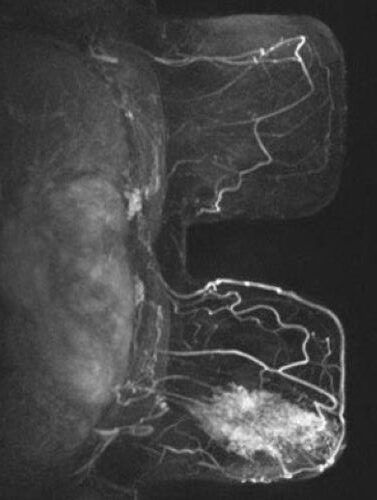

Abbildung zeigt Bilder einer MRT bei Krebs: (1) Wirbelsäulentumor, (2) Knochentumor, (3) Spinalkanaltumor, (4) Mamma-CA (Brustkrebs)

Tumorgewebe ändert die Eigenschaften des betroffenen Gewebes oder wenn es sich um gestreute Tumormetastasen handelt, stellt es sich als Fremdkörpergewebe dar mit anderen Eigenschaften als die Umgebung, die MRT stellt dies technisch als Bildveränderung sichtbar dar und lässt sich somit als Tumor diagnostizieren. Bei zusätzlichen Kontrastmittel-gestützten Bildsequenzen lässt sich zudem das abnormale Durchblutungsverhalten der Tumore erkennen: Das Kontrastmittel ist selbst deutlich als verändertes Signal der Gewebe wahrzunehmen. Tumore können entweder als zeitweise Verstärkung oder Verminderung des Bildsignals im Vergleich zum umgebenden Gewebe abgegrenzt werden.